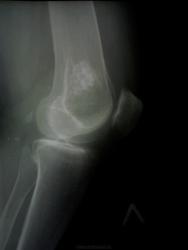

Рис. 194. Обызвествление костного мозга в нижнем метафизе бедренной кости, связанное с переломом.

Больная 50 лет много лет страдает артритом правого коленного сустава, хромает. Имеется атрофия мускулатуры конечности, ограничение подвижности в коленном суставе. Несколько лет назад был перелом бедренной кости.

Рентгенограмма: кости сустава порозны; суставная щель значительно сужена; суставные края костей сустава узурированы; на границе средней и нижней трети бедренной кости следы сросшегося со смещением под углом перелома; в нижнем метафизе кости конгломерат известковых отложений; виден след продольной трещины кости, подходящий к метафизу.

В данном наблюдении обызвествление костного мозга, безусловно, можно связывать с кровоизлиянием, вызванным переломом. Но следует принять во внимание и некоторые биологические особенности - давнее костно-суставное заболевание, остеопороз, - возможно, способствующие обызвествлению гематомы в костном мозгу. Логичнее всего считать наблюдаемые обызвествления костного мозга как последствия некротических асептических процессов в костном мозгу, возникающих в результате рефлекторных расстройств кровообращения в сосудах последнего. Нужно также учитывать индивидуальные особенности организма, возможность расстройства трофики тканей.

Женщина 1952 г.р.,направлена с диагнозом остеоартроз

Энхондрома, инфаркт кости, хондросаркома. Я в заключении такой бы диф. ряд написал.

На мой взгляд имеет место быть "Хрящевая матрица"

А с чего бы это костному мозгу обызвествляться? Больше не энхондрому похоже

+1.Энхондорма? Хондросаркома?? Для уточнения рекомендована КТ коленного сустава.

Большое спасибо за комментарии!Сегодня пациентка принесла архивные снимки обоих коленных суставов,за 2008,2009,2011 года -картина такая же и на тех снимках,а на снимках правого коленного сустава за 2008 год такой же участок(немного меньших размеров) в области метадиафиза большеберцовой кости.Ни МРТ ни КТ никогда не делала.

Энхондрома все же не исключается.